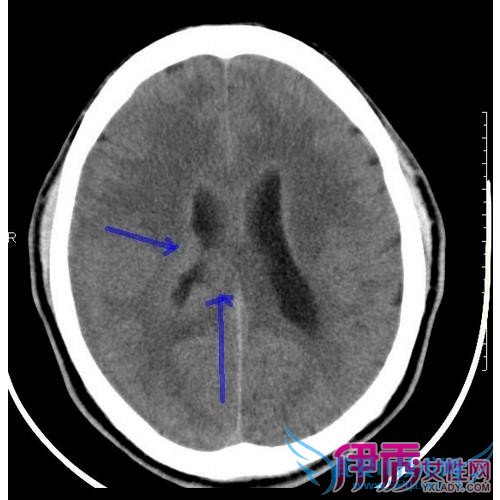

大脑是由上百亿个神经元组成的,而神经元又是由细胞体和神经纤维组成的,细胞体中有细胞核(颜色深),神经纤维中有细胞质(颜色浅)。在大脑中细胞体聚集在大脑表层,看起来颜色深,叫做脑灰质;而神经纤维聚集在大脑内部,看起来颜色浅,叫做脑白质。脑白质病是一种大脑的结构性改变,以中枢神经细胞的髓鞘损害为主要特征,病变累及专门发挥高级大脑功能的白质束。其临床表现从注意力不集中、健忘和个性改变,到痴呆、昏迷甚至死亡。

初步精神状态检查,包括评价注意力不集中的试验、鉴定记忆力障碍的三词延迟回忆试验、评价视觉功能障碍的时钟绘画和评价脑功能的交替运动序列。如果精神状态检查结果可疑,可进一步进行神经精神学测试。如果初步精神状态检查的前两类试验未发现任何缺陷,则可确定无可察觉的大脑损害;如果前两类试验发现异常,可进行大脑神经影像学检查。加权磁共振成像是首选检查手段,是鉴别早期或轻微脑白质病与精神疾病的重要手段,而CT仅能显示重度脑白质损害。